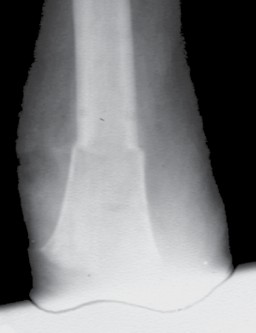

Bei der Operation selbst (Abb. 1–6) geht man so vor, dass zunächst ein zirkulärer Hautschnitt etwa 4 bis 7 cm unterhalb des Tibia-Plateaus erfolgt. Es ist besonders wichtig, darauf zu achten, möglichst viel Haut unterhalb des Gelenkspaltes zu belassen, weil in dieser Region die Haut sich erheblich retrahieren kann. Die Hautnaht muss aber unbedingt ohne Spannung erfolgen. Anschließend präpariert man am Patellaband hoch bis zum Gelenkspalt, eröffnet die Kapsel und durchtrennt dann sukzessive die Kreuzbänder und die Kapsel. Unter fortwährendem Zug am Unterschenkel wird sodann durch das Gelenk die Kapsel bis zur hinteren Kapsel durchtrennt. Dabei werden die auf der Knierückseite liegenden Strukturen geschont. Der Gelenkknorpel wird unberührt belassen. Die bradytrophen Menisci werden entfernt. Die Kniescheibe selbst wird nicht, wie immer wieder in Lehrbüchern beschrieben, an den Kreuzbandstümpfen fixiert, da hieraus oft eine Fehlpositionierung der Kniescheibe unter die Belastungsfläche resultiert. Die Kniescheibe ist in dieser Position nicht endbelastbar, sie verursacht Druckprobleme (s. Abb. 11) und schmerzt. Zudem resultiert hieraus eine Verlängerung des Stumpfes.

Eine exzessiv hypermobile Kniescheibe verursacht in der Prothesenversorgung sekundäre Probleme. Hier ist der Orthopädie-Techniker gefordert. Meist lässt sich eine stark bewegliche Kniescheibe durch eine Art Laufrinne in der Prothese gut in den Griff bekommen. In seltenen Fällen ist eine Entfernung der Kniescheibe notwendig. Auch bei erheblichen retropatellaren Degenerationen ist bereits bei der primären Operation, in seltenen Fällen sekundär die Entfernung der Kniescheibe angezeigt. Gleiches kann aus einer in der Operation zu tief festgenähten Kniescheibe resultieren (Abb. 11).